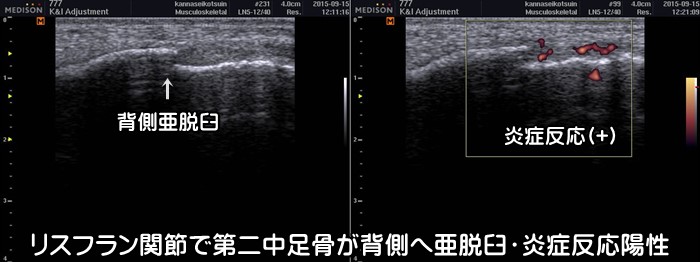

リスフラン関節靭帯損傷

足の甲、特に第2趾に沿って痛みがある場合はリスフラン関節靭帯損傷を疑います。つま先立ちのような状態で体重をかけると痛みが出現します。単なる捻挫と見過ごされやすい少し特殊な靭帯損傷です。